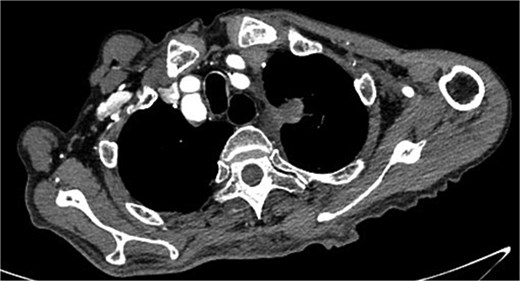

A 68-year-old male was admitted on July 14, 2023, with “intermittent blood in phlegm for over a month.” He had a history of EVAR and underwent right internal iliac aneurysm embolization (Fig. 1A) on July 18, 2019 for an abdominal aortic aneurysm (Fig. 1B). On July 1, 2022, he underwent left iliac artery stent graft implantation due to abdominal pain from a type Ib endoleak (see Fig. 1C). Computed tomography angiography (CTA) findings demonstrated that the maximum diameter of the thoracic aortic aneurysm had reached 72.64 mm and showed a 11.49 mm increase in aortic arch aneurysms over 3 years, which had been reached the established criteria for surgical intervention according to the 2022 ACC/AHA Guideline for the Diagnosis and Management of Aortic Disease [1] (Fig. 1D and E).

(A) Internal iliac artery embolization and stent graft implantation were performed. (B) Preoperative aortic CTA in 2019. (C) Type Ib endoleak from left iliac artery stent graft. (D) CTA shows the diameter of aortic arch aneurysm was 61.15 mm in July 2019. (E) CTA shows the diameter of aortic arch aneurysm was 72.64 mm in July 2022.